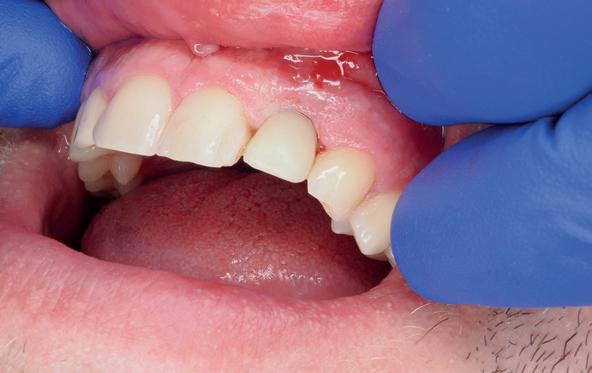

Implantologische behandelingen in het esthetische front vragen meer dan technische vaardigheid alleen. Ze vragen om overzicht, timing, vertrouwen en een team dat als vanzelf samenwerkt onder druk. Juist bij complexe casussen, waarin angst, infectie en hoge esthetische verwachtingen samenkomen, wordt zichtbaar hoe bepalend de rol van de tandartsassistent is.

Deze casus beschrijft een uitgebreide immediate implantaatbehandeling bij een patiënt die door meerdere collega’s werd geweigerd. Niet omdat de mogelijkheden ontbraken, maar omdat de complexiteit vroeg om een perfect afgestemde samenwerking. Het verhaal laat zien hoe de assistent in zo’n traject veel meer is dan een uitvoerende kracht of “mal”, maar een dynamische surgical guide die het proces mede stuurt, bewaakt en mogelijk maakt.De patiënt: wanneer alles samenkomt

Twee weken later zie ik de patiënt terug voor controle van de eerste wondgenezing. De noodprothese mag de eerste twee weken niet gedragen worden en wordt tijdens de controle zorgvuldig aangepast aan de nieuwe situatie. Hiervoor wordt de prothese gedeeltelijk uitgefreesd en voorzien van een Soft Reliner materiaal. Te veel druk op de beide kaken moet ten alle tijden voorkomen worden en heeft effect op de ingroei van de botopbouw. De genezingsperiode duurt tenminste zes maanden voordat verdergegaan kan worden met de tweede fase: de abutment chirurgie. Hierbij wordt extra aandacht besteed aan het herstel van de gekeratiniseerde gingiva rondom de abutments. Dit komt ten goede aan de uitvoering van de mondhygiëne en dus de stabiliteit van de peri-implantaire mucosa. Deze ogenschijnlijk eenvoudige behandeling is essentieel voor de prognose van de implantaten op de lange termijn. Te weinig gekeratiniseerde mucosa maakt zelfzorg (borstelen/interdentaal reinigen) vaker pijnlijk of lastig, waardoor plaque en mucositis makkelijker kunnen ontstaan en blijven over de lange termijn. Dat kan bij patiënten die vatbaar zijn voor peri-implantitis zich vertalen naar crestaal botverlies rondom implantaten. Gek genoeg wordt de essentie van het herstellen van de gekeratiniseerde gingiva rondom implantaten regelmatig genegeerd.

De breedte en kwaliteit van de peri-implantaire mucosa beïnvloeden niet alleen esthetiek, maar met name de uitvoerbaarheid van zelfzorg en de stabiliteit van de mucosale barrière. Consensus reports en meta-analyses laten zien dat een beperkte of afwezige col van gekeratiniseerde peri-implantaire mucosa (vaak gedefinieerd als <2 mm) geassocieerd kan zijn met (1) meer plaque-accumulatie, (2) meer wekedelen-inflammatie, (3) meer mucosale recessie, (4) meer marginaal botverlies en (5) een hogere prevalentie van peri-implantitis.4-6 In de dagelijkse praktijk is dit vooral relevant bij full-arch restauraties waarbij de connectie prothese-abutments en de overgang prothese-mucosa moeilijker te reinigen zijn. Bij onvoldoende gekeratiniseerde mucosa of een ondiepe omslagplooi wordt poetsen vaak pijnlijk, waardoor plaquecontrole onvoldoende is en peri-mucositis gemakkelijk ontstaat. Dit verdedigt de indicatie voor een wekedelen augmentatie als chirurgisch onderdeel van de implantologische behandeling. Streefwaarde van ongeveer ≥2 mm gekeratiniseerde mucosa rondom implantaten wordt in de literatuur vaak gehanteerd.4, 5 Technisch kan dit in de tweede fase (abutmentchirurgie) voorafgaand aan de prothetiek worden uitgevoerd met een apicaal gepositioneerde flap, al dan niet gecombineerd met een gesteelde dan wel een vrij bindweefseltransplantaat (free gingival graft, FGG). FGG geldt als ‘standard of care’ voor voorspelbare toename van gekeratiniseerde mucosa. Xenogene collageenmatrixen kunnen in geselecteerde gevallen een alternatief zijn, bijvoorbeeld om donor site morbiditeit te beperken.4 Waar dikte en contour belangrijk zijn (recessies/esthetiek) wordt vaker een bindweefseltransplantaat overwogen.